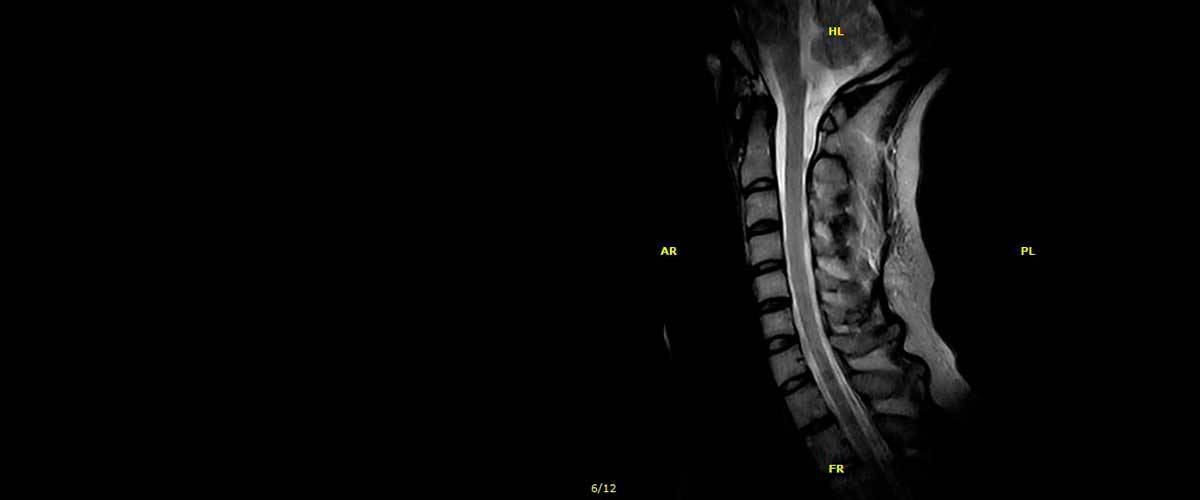

Contamos con equipos de resonancia magnética musculo-esquelética capaces de realizar exámenes con descarga de peso o bipedestación.

En nuestros centros se realizan estudios y diagnósticos de resonancia magnética musculo-esquelética

de Resonancia ,Magnética Musculo-Esquelética, de la marca italiana Esaote, es único en su diseño ya que nos permite realizar exámenes en bipedestación (el paciente estará de pie, para que se tenga otra perspectiva del comportamiento del cuerpo durante el examen).